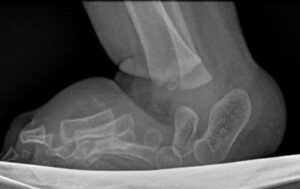

Foot surgery in arthrogryposis

Foot deformities are common in all forms of arthrogryposis, and particularly in amyoplasia and the distal forms.

The most common forms are congenital clubfoot equinovarus and congenital vertical talus; equinus deformities are rarer.

For the equinovarus foot , the interventions include, depending on the patient’s age, the severity of the deformity and previous treatments:

- Ponseti method: correction using progressive casts. The results obtained are inferior to those achieved with idiopathic clubfeet. Specifically, the percentage of feet that cannot achieve complete correction and require surgical release is higher (and this occurs more frequently in amyoplasia and less frequently in distal arthrogryposis), and the recurrence rate is higher. For this reason, even after the deformity has been corrected, it is important to use both Ponseti and AFO braces for extended periods, combined with physiotherapy.

- extensive soft tissue release, with tendon resections

- osteotomies (Evans, Lichtblau, etc.)

- talectomies, which some authors indicate as primary treatment, but which in our opinion should be used with caution and should be reserved only as a last choice treatment in the foot that has already relapsed

- correction using the Ilizarov external fixator , which allows progressive corrections for the most severe and complex deformities

For forms of congenital vertical talus, the following are indicated, after initial non-invasive treatment/Ponseti method:

- soft tissue release (medial, posterior and lateral) with reduction of dislocations

- corrective osteotomies, talectomies, Grice procedure

- double/triple arthrodesis once skeletal maturity has been reached, in the case of recurrence/incomplete correction

In any case, the deformities tend to be rigid and resistant to treatment and have a high rate of recurrence, therefore periodic checks and adequate support (insoles, AFO braces, orthopedic footwear) will be necessary.